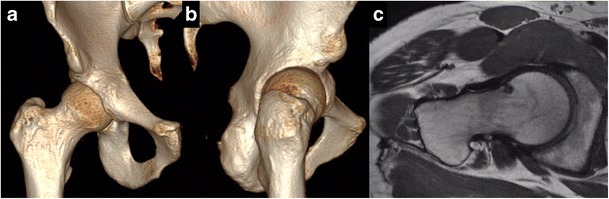

Fig. 1.

Predominant cam-type FAI of the right hip in 18-year-old pitcher with hip pain. (A) 3D CT scan with cam lesion located from 1:30–3:00, alpha angle of 64° and reduced femoral anteversion of 5°. (B) Reveals a Type-II AIIS. (C) Axial proton density MRI of the right hip reveals impingement cyst along anterior femoral head-neck junction at approximately 2:00